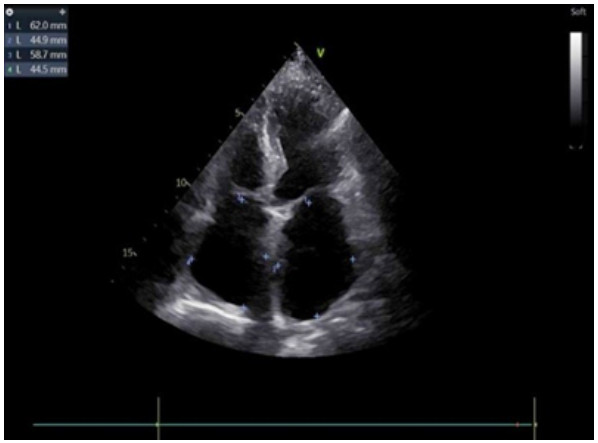

辅助检查:常规心电图示心房颤动。床旁经胸超声心动图示:原左房血栓影未显示(见图 3)。

注:左房内团块样回声影未见显示 图 3 患者本次入院当天常规经胸腔超声心动图